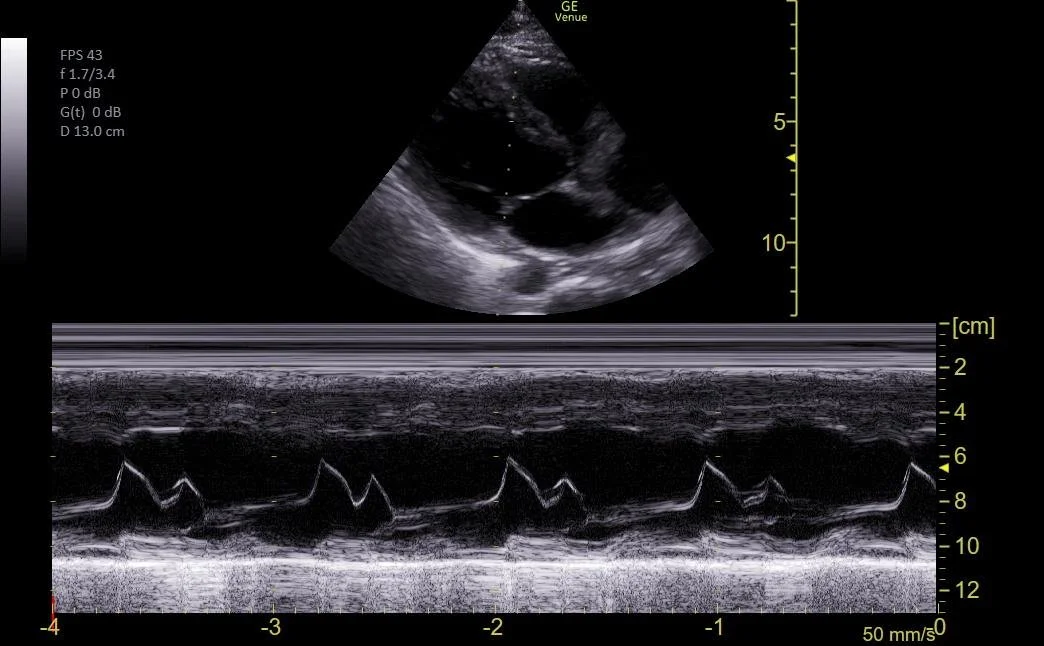

Parasternal long view showing the EPSS (end-point septal separation) using M-Mode through the mitral valve leaflet to evaluate the EF.

c/o VIctoria Gonzalez, MD